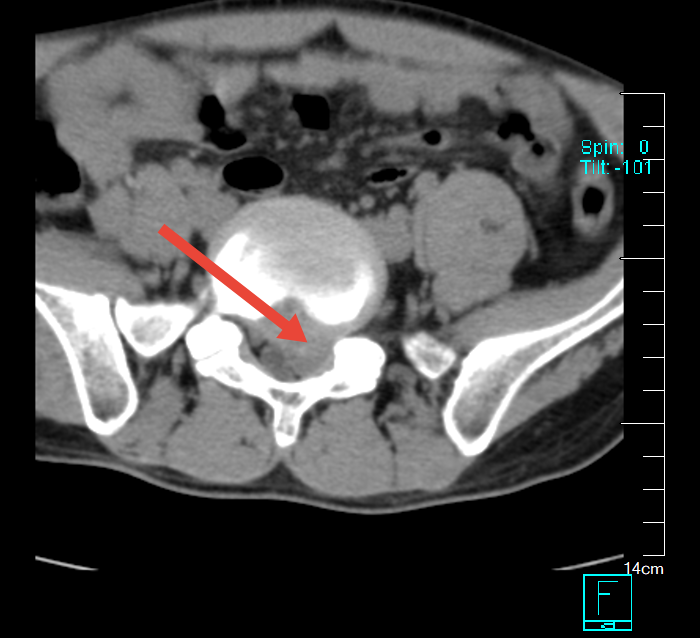

“腰杆像断了,腿像过电一样麻”——这是34岁舒先生近20天来的真实感受。五年来反复发作的腰腿痛,在春节前突然“升级”,左下肢放射痛让他几乎无法站立。影像检查结果令人揪心:腰椎间盘不止突出,更疑似“脱出”,神经根受压十分严重。

术前